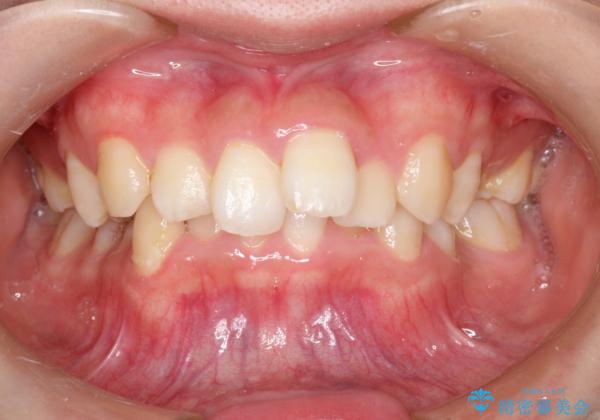

重度のガタガタのインビザラインによる非抜歯矯正

ガタガタの度合いが大きかったので少し時間がかかりましたが、非常に協力的な患者様でしたので、抜歯をせず計画通りに治療を終えることができました。